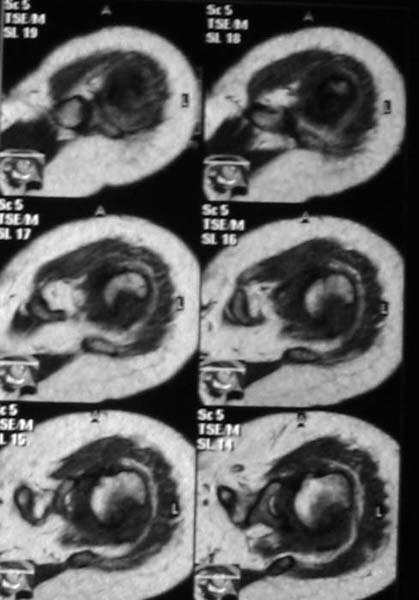

Активное отведение 80 гр., при пальпации - головка плечевой кости безболезненно вправляется и тут же самостоятельно вывихивается. Наложена косыночная иммобилизация, рентгенография (r3) и МРТ.В нашем диагностическом центре МРТ исследование плечевого сустава выполнено впервые, опыта у нас маловато :(.Вопросы: уточнение диагноза? какие исследования провести? тактика лечения?

Из того, что видно на недостаточно качественно отсканированных МРТ - нижний подвывих плеча и синовиит. Непонятный очаг по заднему контуру головки плеча (то ли артефакт, то ли косой срез, проходящий между головкой и большим бугорком). Сухожилия вращательной манжетки выглядят целыми. Неправильная форма нижней части labrum glenoidale - разрыв ?

МРТ должен показать разрыв манжетки, но признаться я не большой эксперт по чтению МРТ сканов, хотя затемнение, отек мягких тканей по задней поверхности плеча видны Обычные рентгенограммы демонстрируют остеолизис в области большого бугорка.

1. На рентгене - нижний подвывих плеча и очаг остеолиза суставного бугорка с четкими контурами (вдавленный перелом на фоне остеопороза ? доброкачественная опухоль? аваскулярный некроз ? (хотя ни разу не слышал об аваскулярном некрозе плеча..)

2.выраженный выпот в полости сустава

Судя по снимкам, речь идTт о типичном случае Hill-Sachs Lesion. По этому поводу я позволю себе некоторый экскурс:

97 % всех вывихов плеча происходит по механизму комбинации отведения, разгибания и наружной ротации (А. Гринспан). В момент вывиха головка плеча ударяет о нижний край гленоида, что ведет к вдавленному или компрессионному перелому одной или обеих структур. Чаще всего, однако, повреждение возникает в задней латеральной области головки плечевой кости на переходе от головки к шейке. Этот диагноз можно выставить на основании рентгеновского снимка в переднезадней проекции с внутренней ротацией плеча. Несколько реже видно повреждение гленоида о передненижний перелом края. То, что мы называем Bankart Lesion. Это повреждение видно на ре. снимке в п.з. проекции при нейтральной позиции плеча. Разумеется хрящевые и мягкотканные повреждения (в смысле Банкарт) мы увидим лучше всего на ЯМР.

Учитывая описанную клинику, речь идTт о комбинации патологии. К сожалению, учитывая качество снимков NMR, я не могу провести достаточно точную верификацию состояния нижнего края гленоида, что впрочем, не меняет рекомендации. Для определения состояния РМ и дополнить исследование УЗИ мягких тканей плеча. В опытных руках достаточно информативное и дешевое исследование.